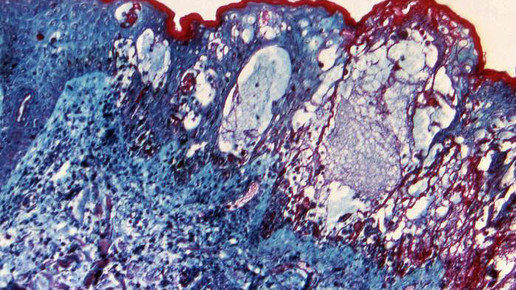

Seit Längerem ist ein Zusammenhang zwischen Gürtelrose und Windpocken bekannt. Der erste Kontakt mit dem Erreger Varizella zoster findet meist im Vorschulalter durch eine Tröpfcheninfektion statt. Nach etwa zwei Wochen entsteht ein juckender Ausschlag auf der Haut. Sind die Windpocken überstanden, wandern die Viren in die Hirnnerven und Nervenwurzeln des Rückenmarks. In den Nervenknoten verbleiben sie in einer Art „Schlaf“. Werden sie durch Stress, UV-Strahlung, ein schwaches Immunsystem oder durch das erreichte höhere Alter reaktiviert, entsteht eine Gürtelrose.

Die Reinfektion tritt lokal begrenzt beispielsweise an Brust, Bauch, Rücken oder Kopf auf. Besonders gefährlich kann es werden, wenn die Viren in Auge oder Ohr eine Gürtelrose hervorrufen. Behandelt wird lokal mit Lösungen oder Salben, die einen austrocknenden Effekt haben, und systemisch mit Virustatika wie Aciclovir, Valaciclovir sowie Brivudin.